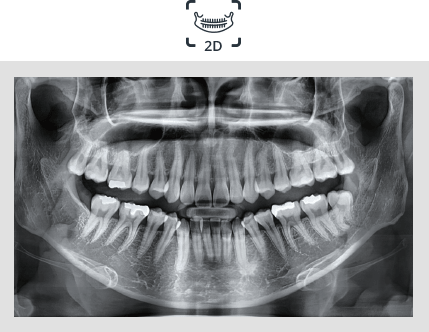

El innovador FOV proporciona un volumen en forma de arco que muestra una vista más amplia de la dentición en comparación con otros dispositivos del mismo FOV.

Normalmente, una imagen de 10x8.5 muestra el diente No.8. Sin embargo, cuando los terceros molares están tumbados sobre su lado hay una gran posibilidad de que el diente se corte de la imagen.

El “volumen en forma de arco” elimina esta posibilidad y muestra el área de dentición oculto.